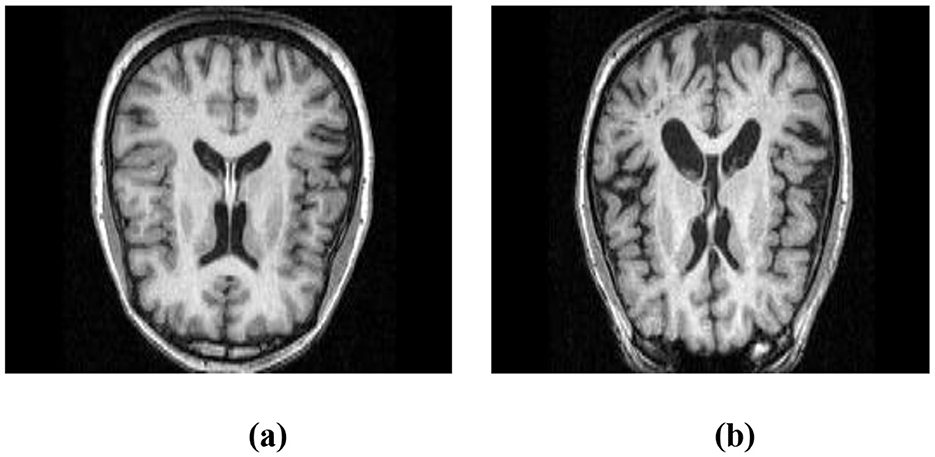

To demonstrate the utility of MRI in this context, Figure 1a shows a structural MRI scan of a healthy subject, while Figure 1b illustrates an AD-affected brain. Clear differences in structural integrity can be observed, highlighting the importance of MRI for early-stage detection.

Figure 1. Structural MRI scans illustrating brain morphology. (a) Non-AD brain image. (b) AD brain image.